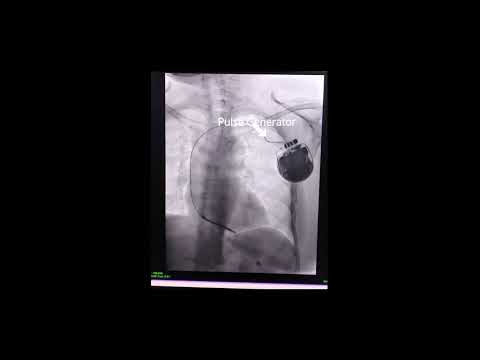

An Automated Implantable Cardioverter Defibrillator (AICD) is a small device implanted in the chest to monitor heart rhythm and prevent sudden cardiac arrest (SCA) in high-risk patients. The AICD continuously tracks heartbeats, automatically delivering a shock to restore normal rhythm if a dangerous arrhythmia is detected. AICD implantation is a minimally invasive procedure, typically performed under local anesthesia, where the device is positioned under the skin, with leads extending into the heart to monitor and regulate rhythm.

The main purpose of an AICD is to prevent sudden cardiac death by detecting and correcting life-threatening heart rhythms. Patients with severe arrhythmias, heart failure, or a family history of sudden cardiac death often qualify for an AICD to manage abnormal heart rhythms and provide a constant safeguard against SCA. Unlike pacemakers, which only manage slower heart rhythms, an AICD can address fast and irregular rhythms, automatically providing therapy when the heart rate becomes dangerously high.

The AICD leads are delicate wires that transmit electrical signals from the heart to the device. Occasionally, these leads may shift or become dislodged after surgery, which can impact the device’s effectiveness. Lead displacement can be corrected with a follow-up procedure to reposition the leads. Following post-surgery guidelines and avoiding sudden arm movements can help prevent this issue.